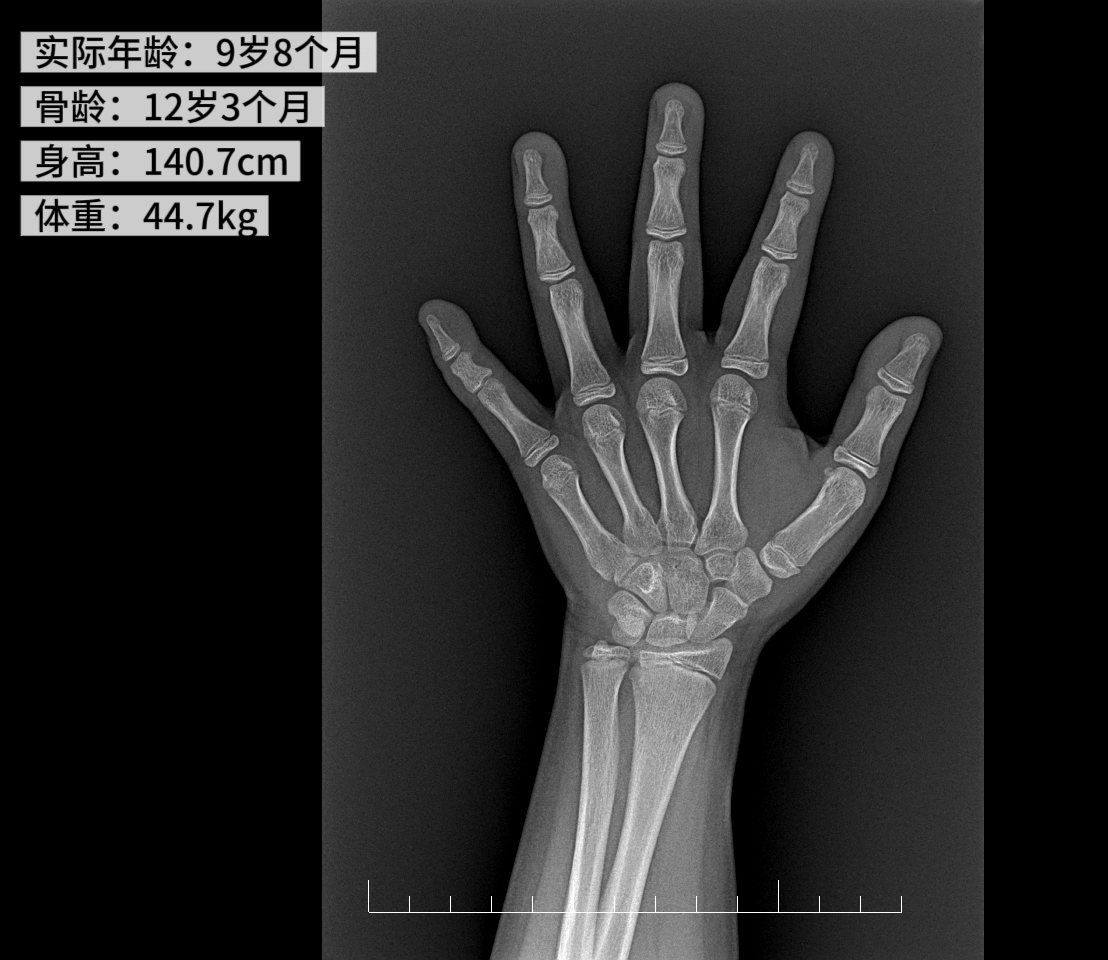

医生为小婷做了全面检查,结果显示 9.8 岁的小婷,身高 140.7 cm(P50),体重 44.7 kg(>P97),BMI 22.8(>P97)。更让人揪心的是孩子的骨龄已经达到 12 岁 3 个月!子宫、卵巢发育已经很成熟,最终小婷诊断为:「性早熟」。

4、骨龄超前:实际年龄小于骨龄 1 岁以上。